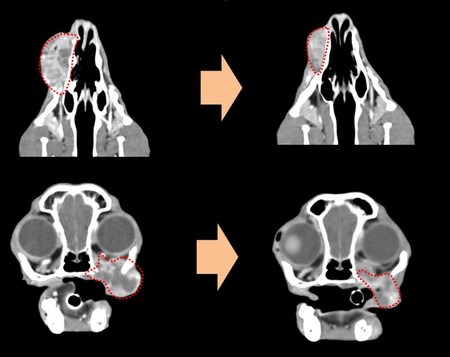

반려견의 구강종양은 비교적 자주 발생하는 종양으로 상악골이나 하악골의 골침습이 심한 경우 수술적 절제가 불가능한 경우가 많다. 특히 구강이라는 위치로 인해 종양이 큰 경우 구강 출혈이나 연하장애가 발생하여 환자의 삶의 질이 많이 떨어지게 된다.

전성훈 센터장은 구두 발표에서 “조직 검사를 통해 절제 불가능한 악성 구강종양이 진단된 환자를 대상으로 구강종양 색전술을 적용한 결과, 4주간의 short-term follow up 기간 동안 종양의 크기는 평균 30.89% 감소했고, 구강출혈, 식욕부진 등의 임상 증상이 소실됐다. 또한 모든 환자들이 시술 당일 퇴원하였으며, 심각한 부작용은 관찰되지 않았다”고 설명했다.